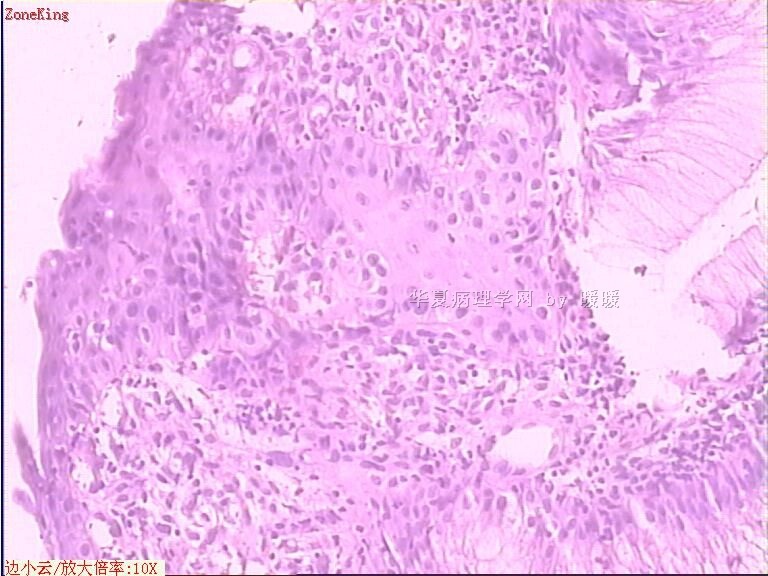

简要病史:  胃镜见,食道下段齿状线上可见一圆形隆起,有蒂,表面光滑,大小0.5X0.5X0.3cm.

各位老师,胃粘膜处出现的鳞状上皮有问题么?

• 贲门息肉?图1

图1

正好是齿状线腺鳞交界处粘膜

可能是炎症刺激所致,不敢报恶性。

鳞状上皮没大问题,可能受炎症影响,稍有增生.

没有发现恶性证据,小心点儿可以拖个尾巴,譬如伴轻度异型增生。

可能是炎症刺激下上皮鳞状化生

慢性炎症

本帖最后由 于 2009-11-21 09:51:00 编辑   谢谢各位老师指点,最终诊断为:贲门慢性炎症,伴局灶细胞轻度异型增生。